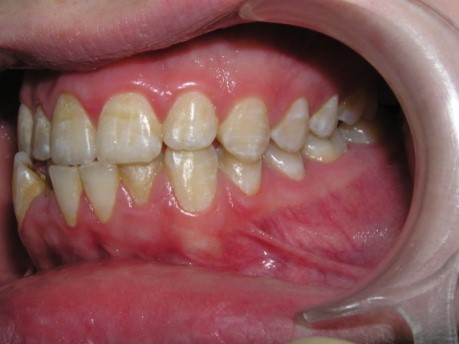

Pic.10. Lingual position of teeth 32 and 42.

The crowding of the lower frontal

teeth reduces the resistance of the teeth to the carious process, creates

conditions for the development of periodontal diseases, and the formation of

periodontal pockets.